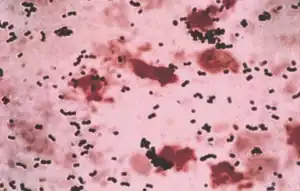

Streptococcus agalactiae- Gram stain | |

As mentioned, S. agalactiae is a Gram-positive coccus with a tendency to form chains, beta-haemolytic, catalase-negative, and facultative anaerobe. GBS grows readily on blood agar plates as microbial colonies surrounded by a narrow zone of β-haemolysis. GBS is characterized by the presence in the cell wall of the group B antigen of the Lancefield classification (Lancefield grouping) that can be detected directly in intact bacteria using latex agglutination tests.[19][20][21]